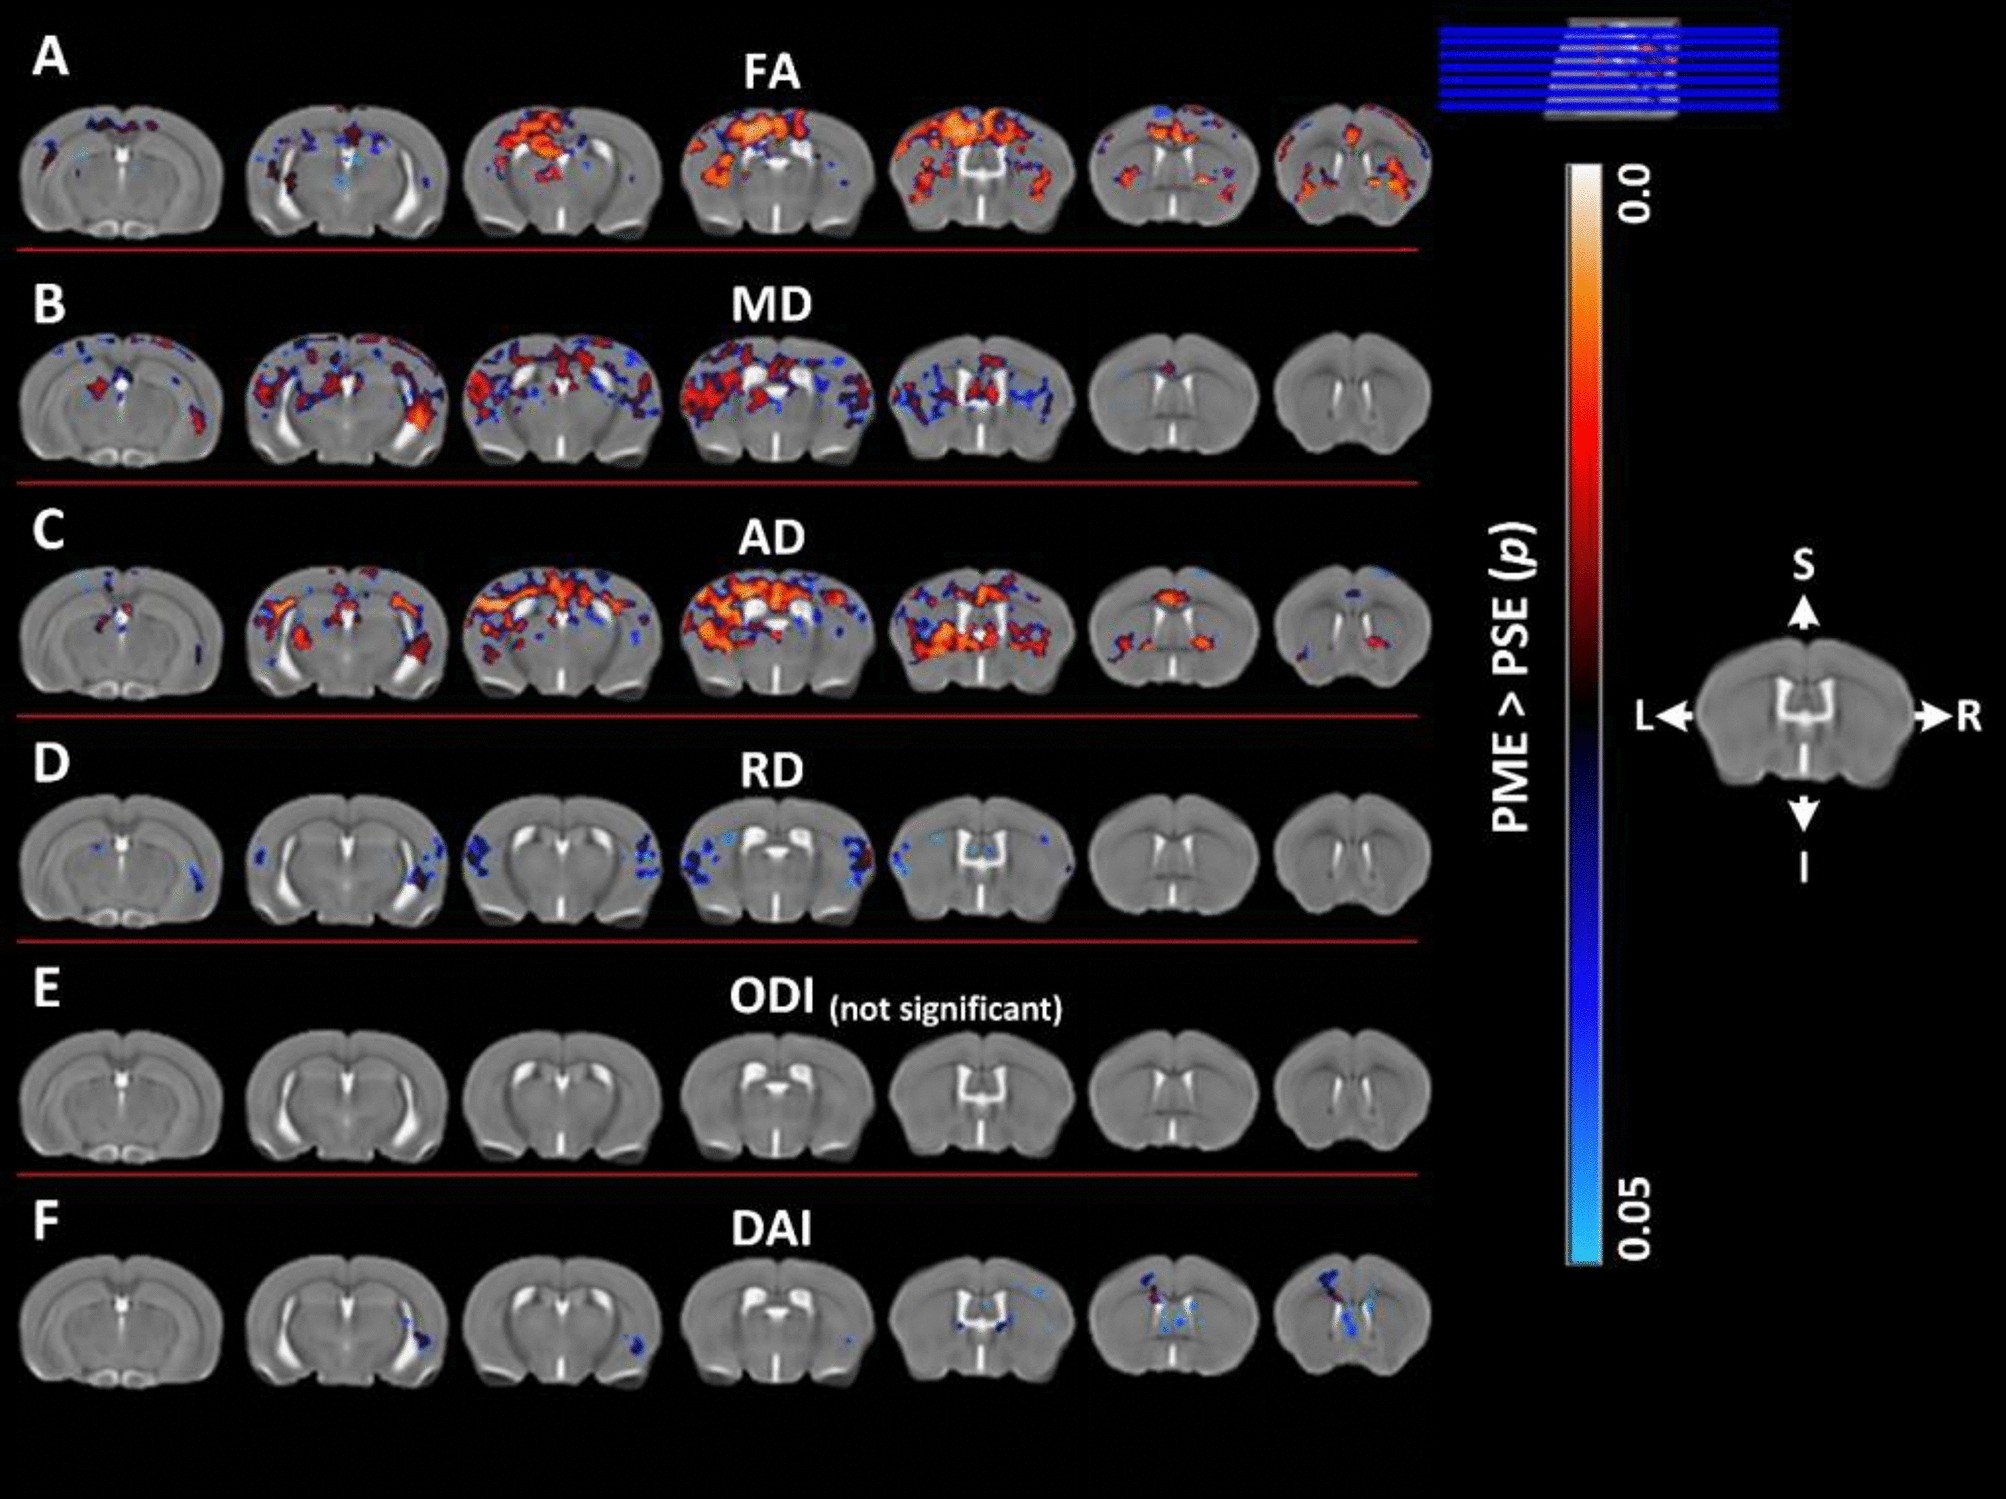

Figure 3

Voxel-wise statistical maps using DTI and NODDI derived parametric maps. Clusters depicted in false color indicate regions where PME (n = 15) animals exhibited significantly higher values compared to PSE (n = 15). The results were family-wise error corrected for multiple comparisons (p < 0.05). Variation in color maps highlight the degree of significance. The results are overlayed on a study specific B0 template for better visualization. FA: fractional anisotropy, MD: mean diffusivity, AD: axial diffusivity, RD: radial diffusivity, ODI: orientation dispersion index and DAI, dispersion anisotropy index. L and R indicate anatomical orientation: Left–Right. S and I indicate anatomical orientation: superior–inferior.